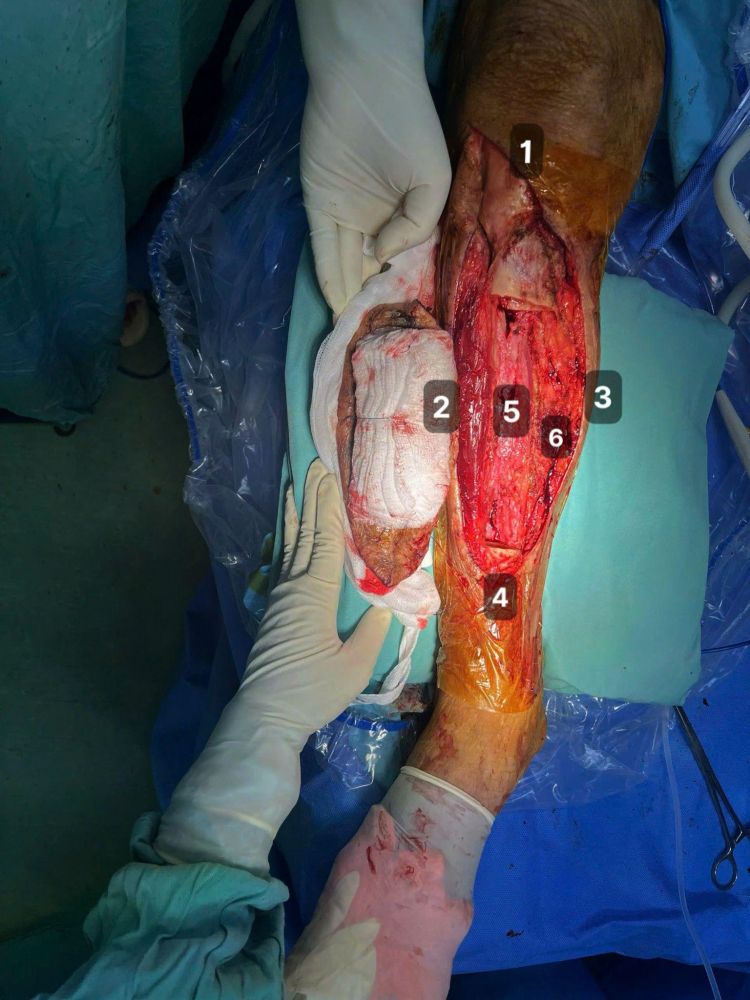

Hình 4: Phần khuyết hỗng phần mềm và xương sau khi cắt bỏ tổn thương nguyên khối bao gồm xương và mô mềm; lấy 6 mẫu xung quanh để làm sinh thiết lạnh bao gồm: 1, 2, 3, 4: rìa cắt ở trên, dưới, trong, ngoài khối tổn thương; 5, 6 tương đương với bao ngoài bó mạch chày trước và chày sau